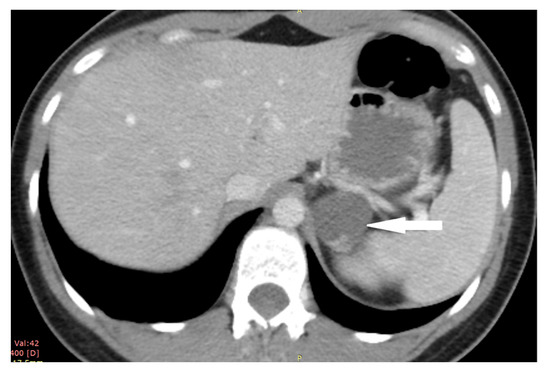

2.2. Case 2